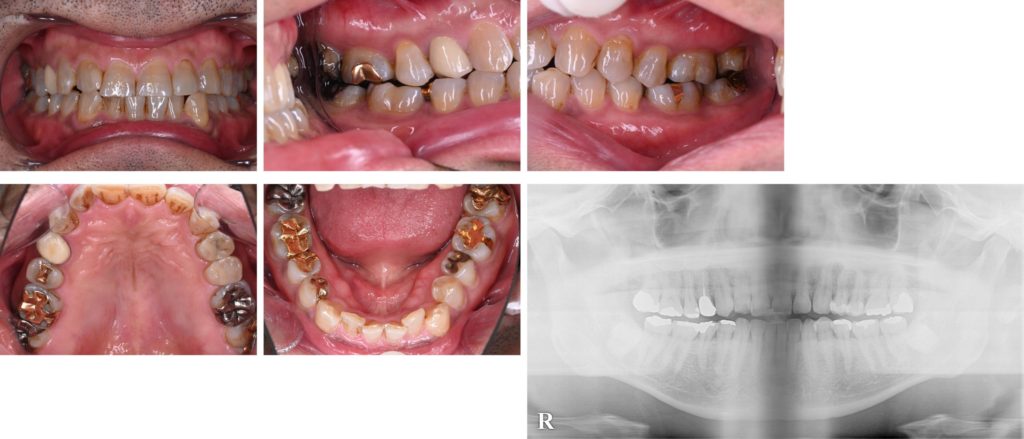

Before

| 診断名 | 補綴物下の二次う蝕(歯肉縁下う蝕含む)・前歯部審美障害(咬耗による歯牙形態異常および歯牙の色調) |

| 年齢・性別 | 57歳 男性 |

| 治療期間・回数 | 22ヶ月 |

| 治療方法 | 基礎治療、矯正治療(インビザラインにて)後、デジタルデータを元にトップダウンで理想的な歯牙形態をシミュレーションし、モックアップ→プロビジョナルレストレーション装着後確認作業を行い、全顎的接着修復を行なった。 |

| 費用 | 3,000,000円 |

| 注意点 | 矯正治療期間中の発音や咀嚼への影響、補綴処置による歯質削除、修復物の破損や脱離の可能性がある |